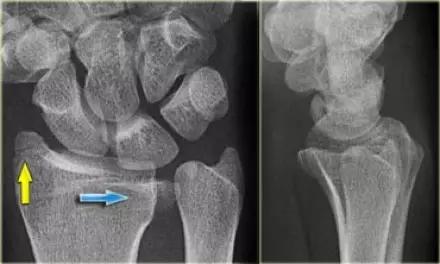

5. Chauffeur 骨折/ Hutchinson 骨折

桡骨干的斜形骨折,早期有机械性弯曲,进而通过逆性外力导致的斜形骨折。指桡骨茎突受舟骨撞击的剪切骨折形成带关节面的三角形骨折。

Essex-Lopresti 损伤。前后位(A)和侧位(B)示桡骨头关节内骨折(白色实线箭头);(C~E)伤后 1 个月复诊,患者诉腕关节疼痛,X 线(C,D)发现下尺桡关节脱位,(E)CT 进一步证实损伤的存在 (来源:Radiol Clin North Am. 2015 Jul;53(4):717-36)